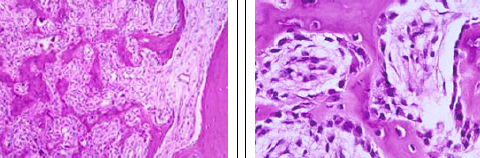

How well did you know this?

highly cellular, sheets of round to polygonal cells; multiple small foci of immature bluish-pink chondroid give a lobular appearance; multinucleated giant cells; chicken-wire (right photo) calcification